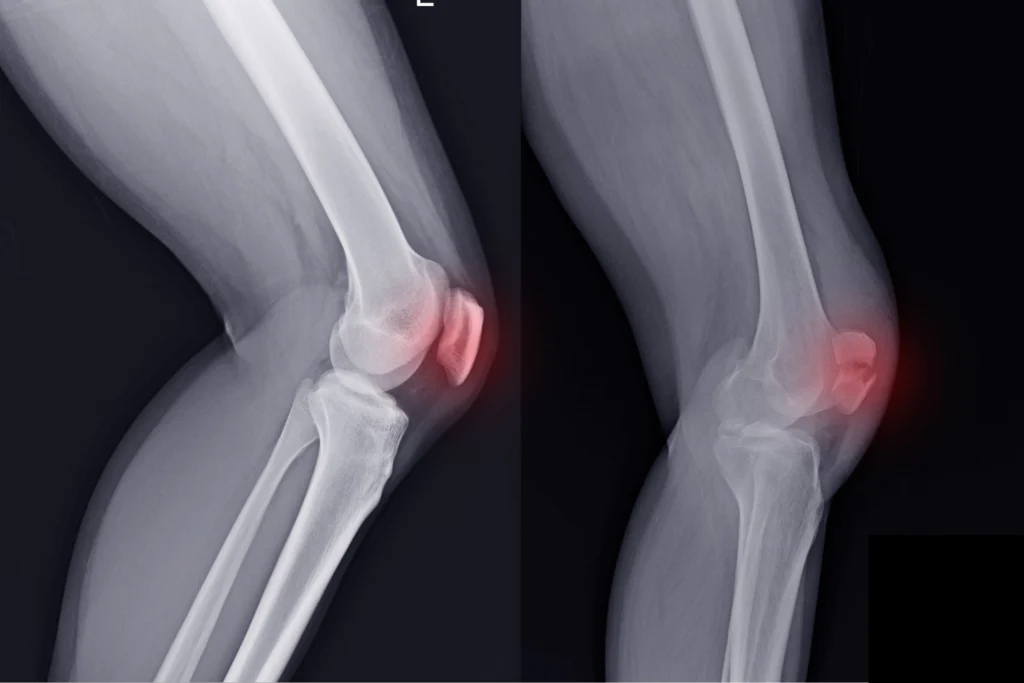

Have you ever gone for a run and noticed your knee pain flares up—and then feel fine a day or two later? It turns out, there may be a surprising reason: water inside the bone of your kneecap (patella).

The researchers used fancy MRI tech that can actually measure how much water is in your bone. That’s how they found this surprising link between water content levels and pain.

Water content in the kneecap bone also increased after running.

After 48 hours of rest, both the pain and bone water levels returned to normal.

In other words, the pain people felt after running could be explained by the increased pressure in the bones due to the increase in water levels in the knee cap. How is that possible? Read the next paragraph on why increased water content in the bone matter.

When you repeatedly load your knee, like during running, there\’s less time for the natural fluids within the bone to drain away. This will result in an increased fluid amount in your knee. Think of this fluid build up as small levels of swelling which can stimulate your nerves. Your nerves are sensitive to pressure, so when the pressure goes up, they contribute to that sharp or arching pain we call PFP.